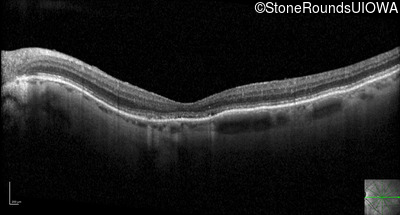

Optical Coherence Tomography - Left - 20/250

Exemplar / OCT Stack

OCT Stack